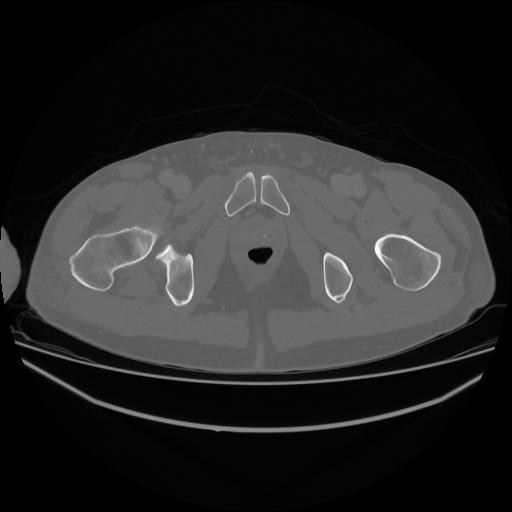

5 CUERPO,CE,Vol,1.0,CUERPO,,